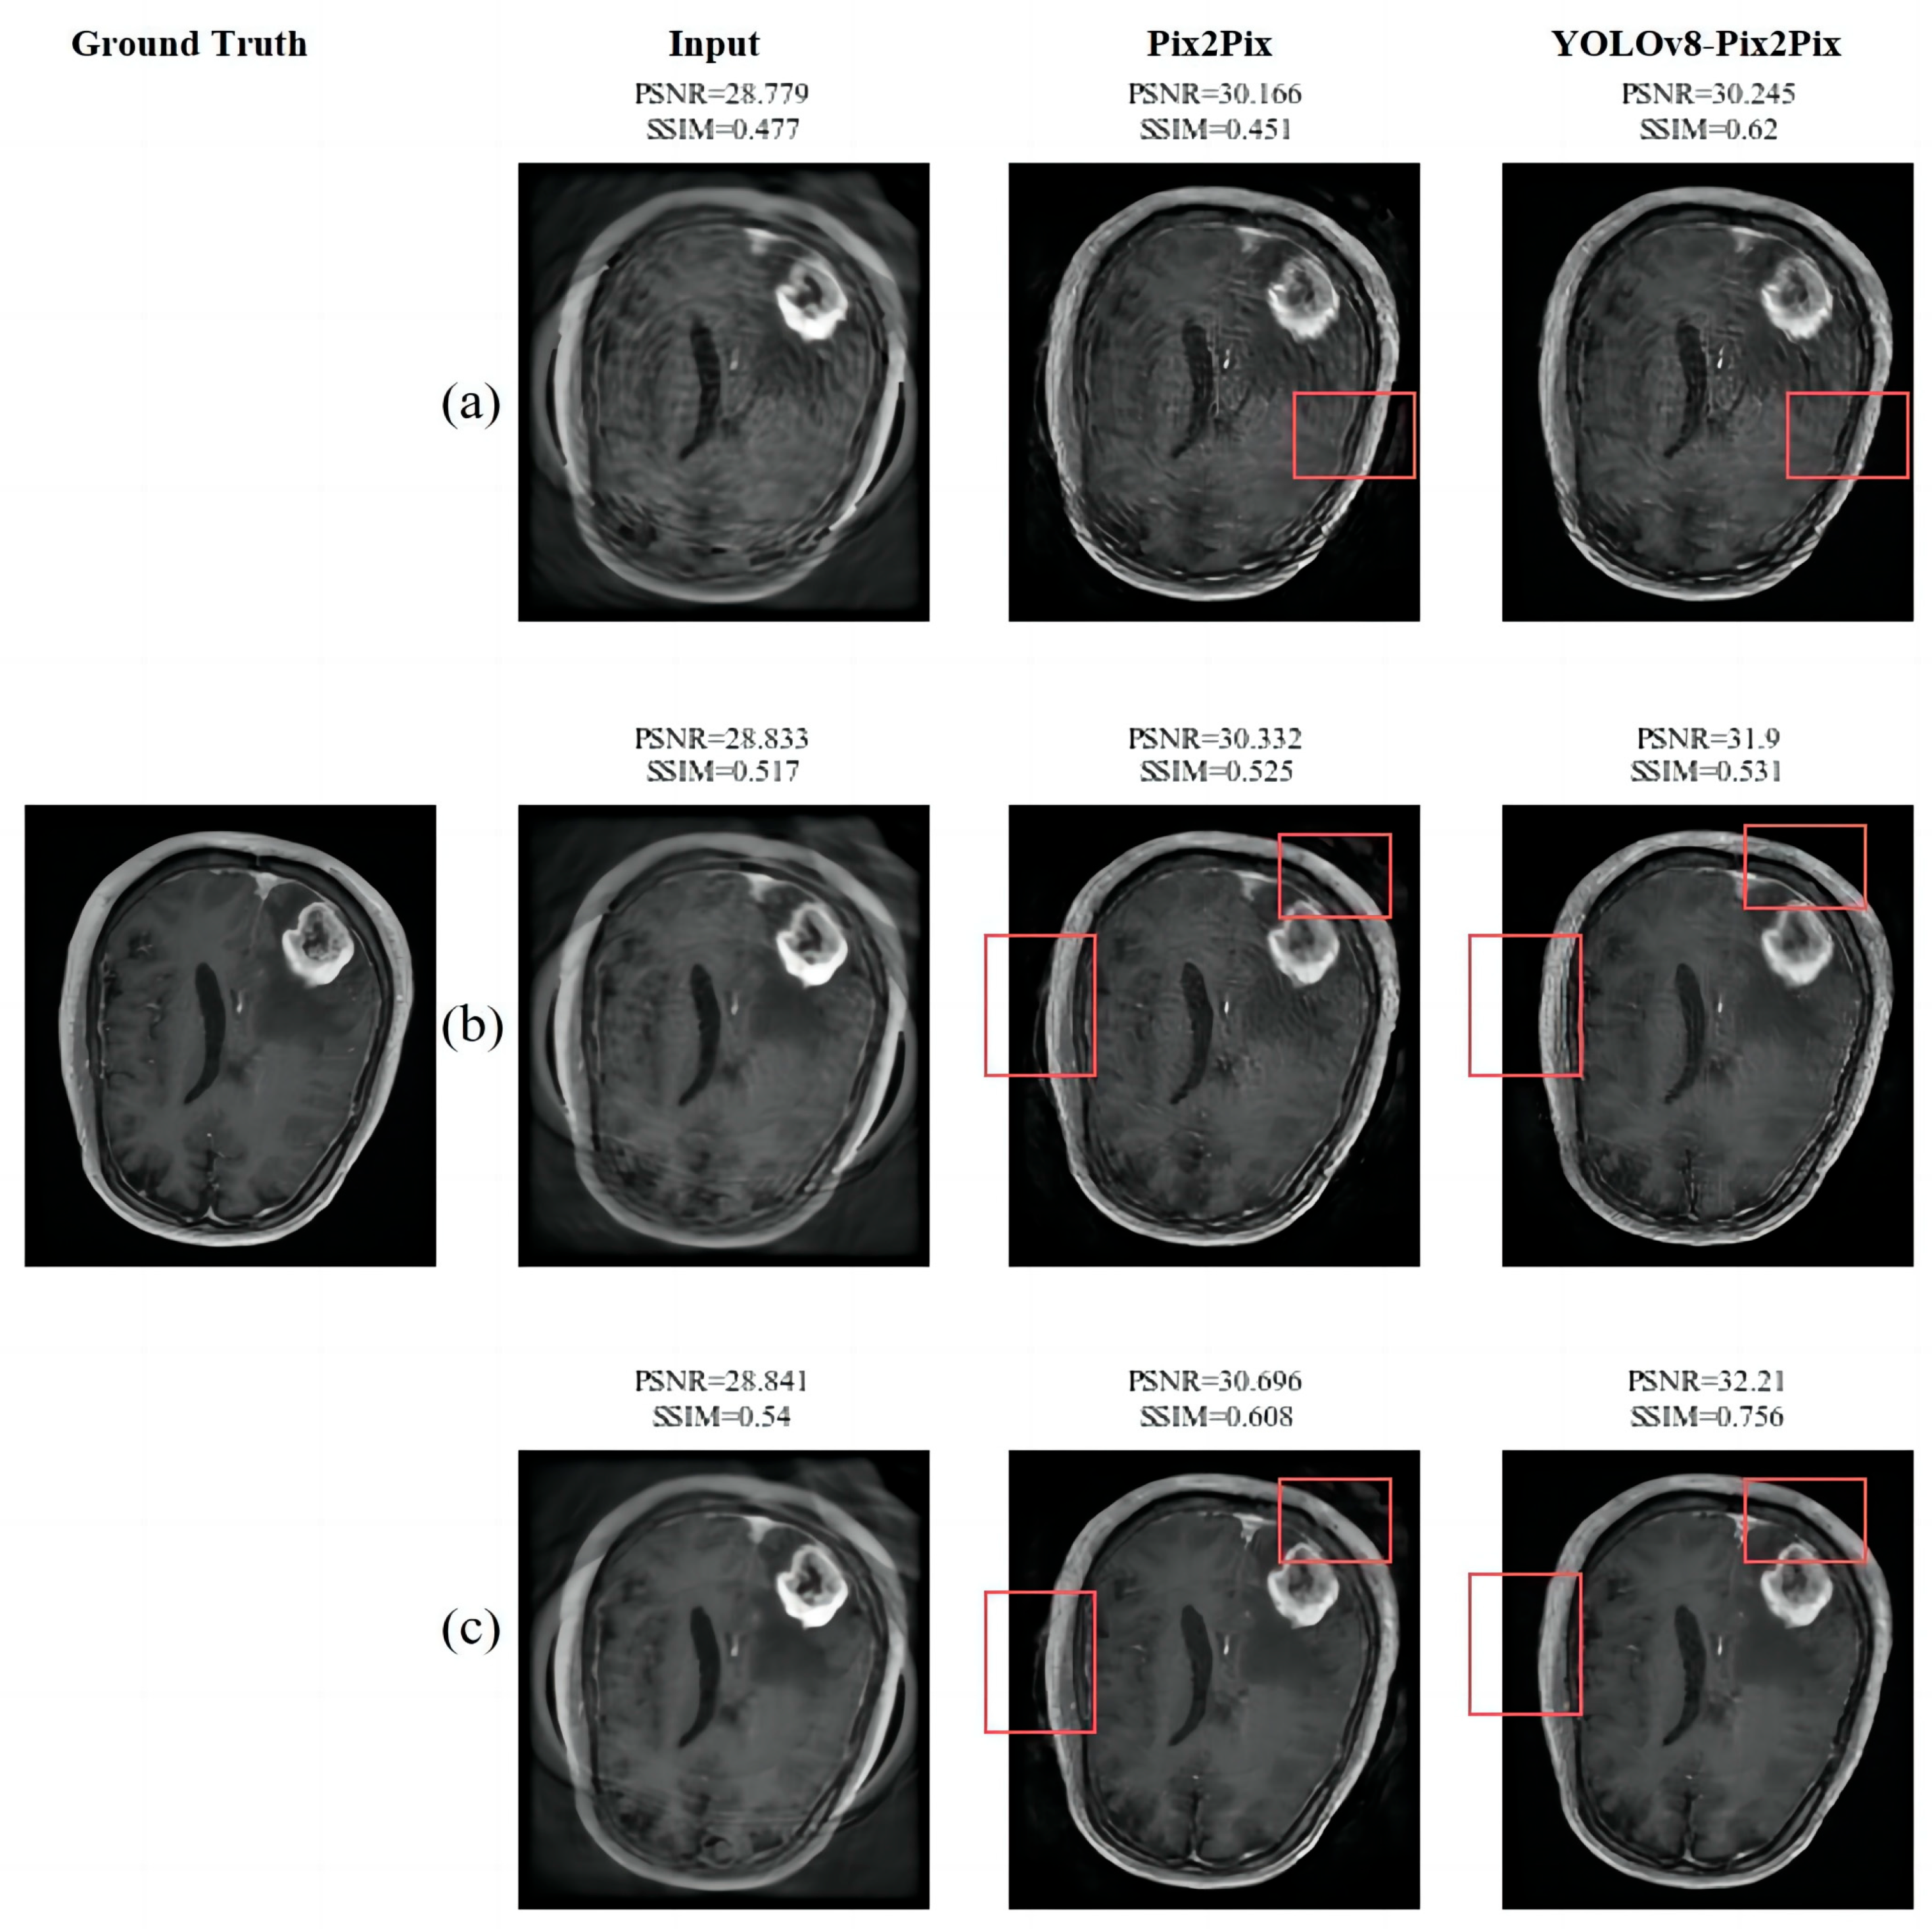

3.3.1. The Experimental Results and Analysis of the Removal of Artifacts

| TR | Gaussian Filter | Cyclegan | Pix2Pix | YOLOv8 | YOLOv8-Cyclegan | YOLOv8-Pix2Pix | |

|---|---|---|---|---|---|---|---|

| PSNR | 28.918 | 28.821 | 29.998 | 30.421 | 29.113 | 29.568 | 31.459 |

| SSIM | 0.566 | 0.526 | 0.571 | 0.612 | 0.491 | 0.513 | 0.650 |